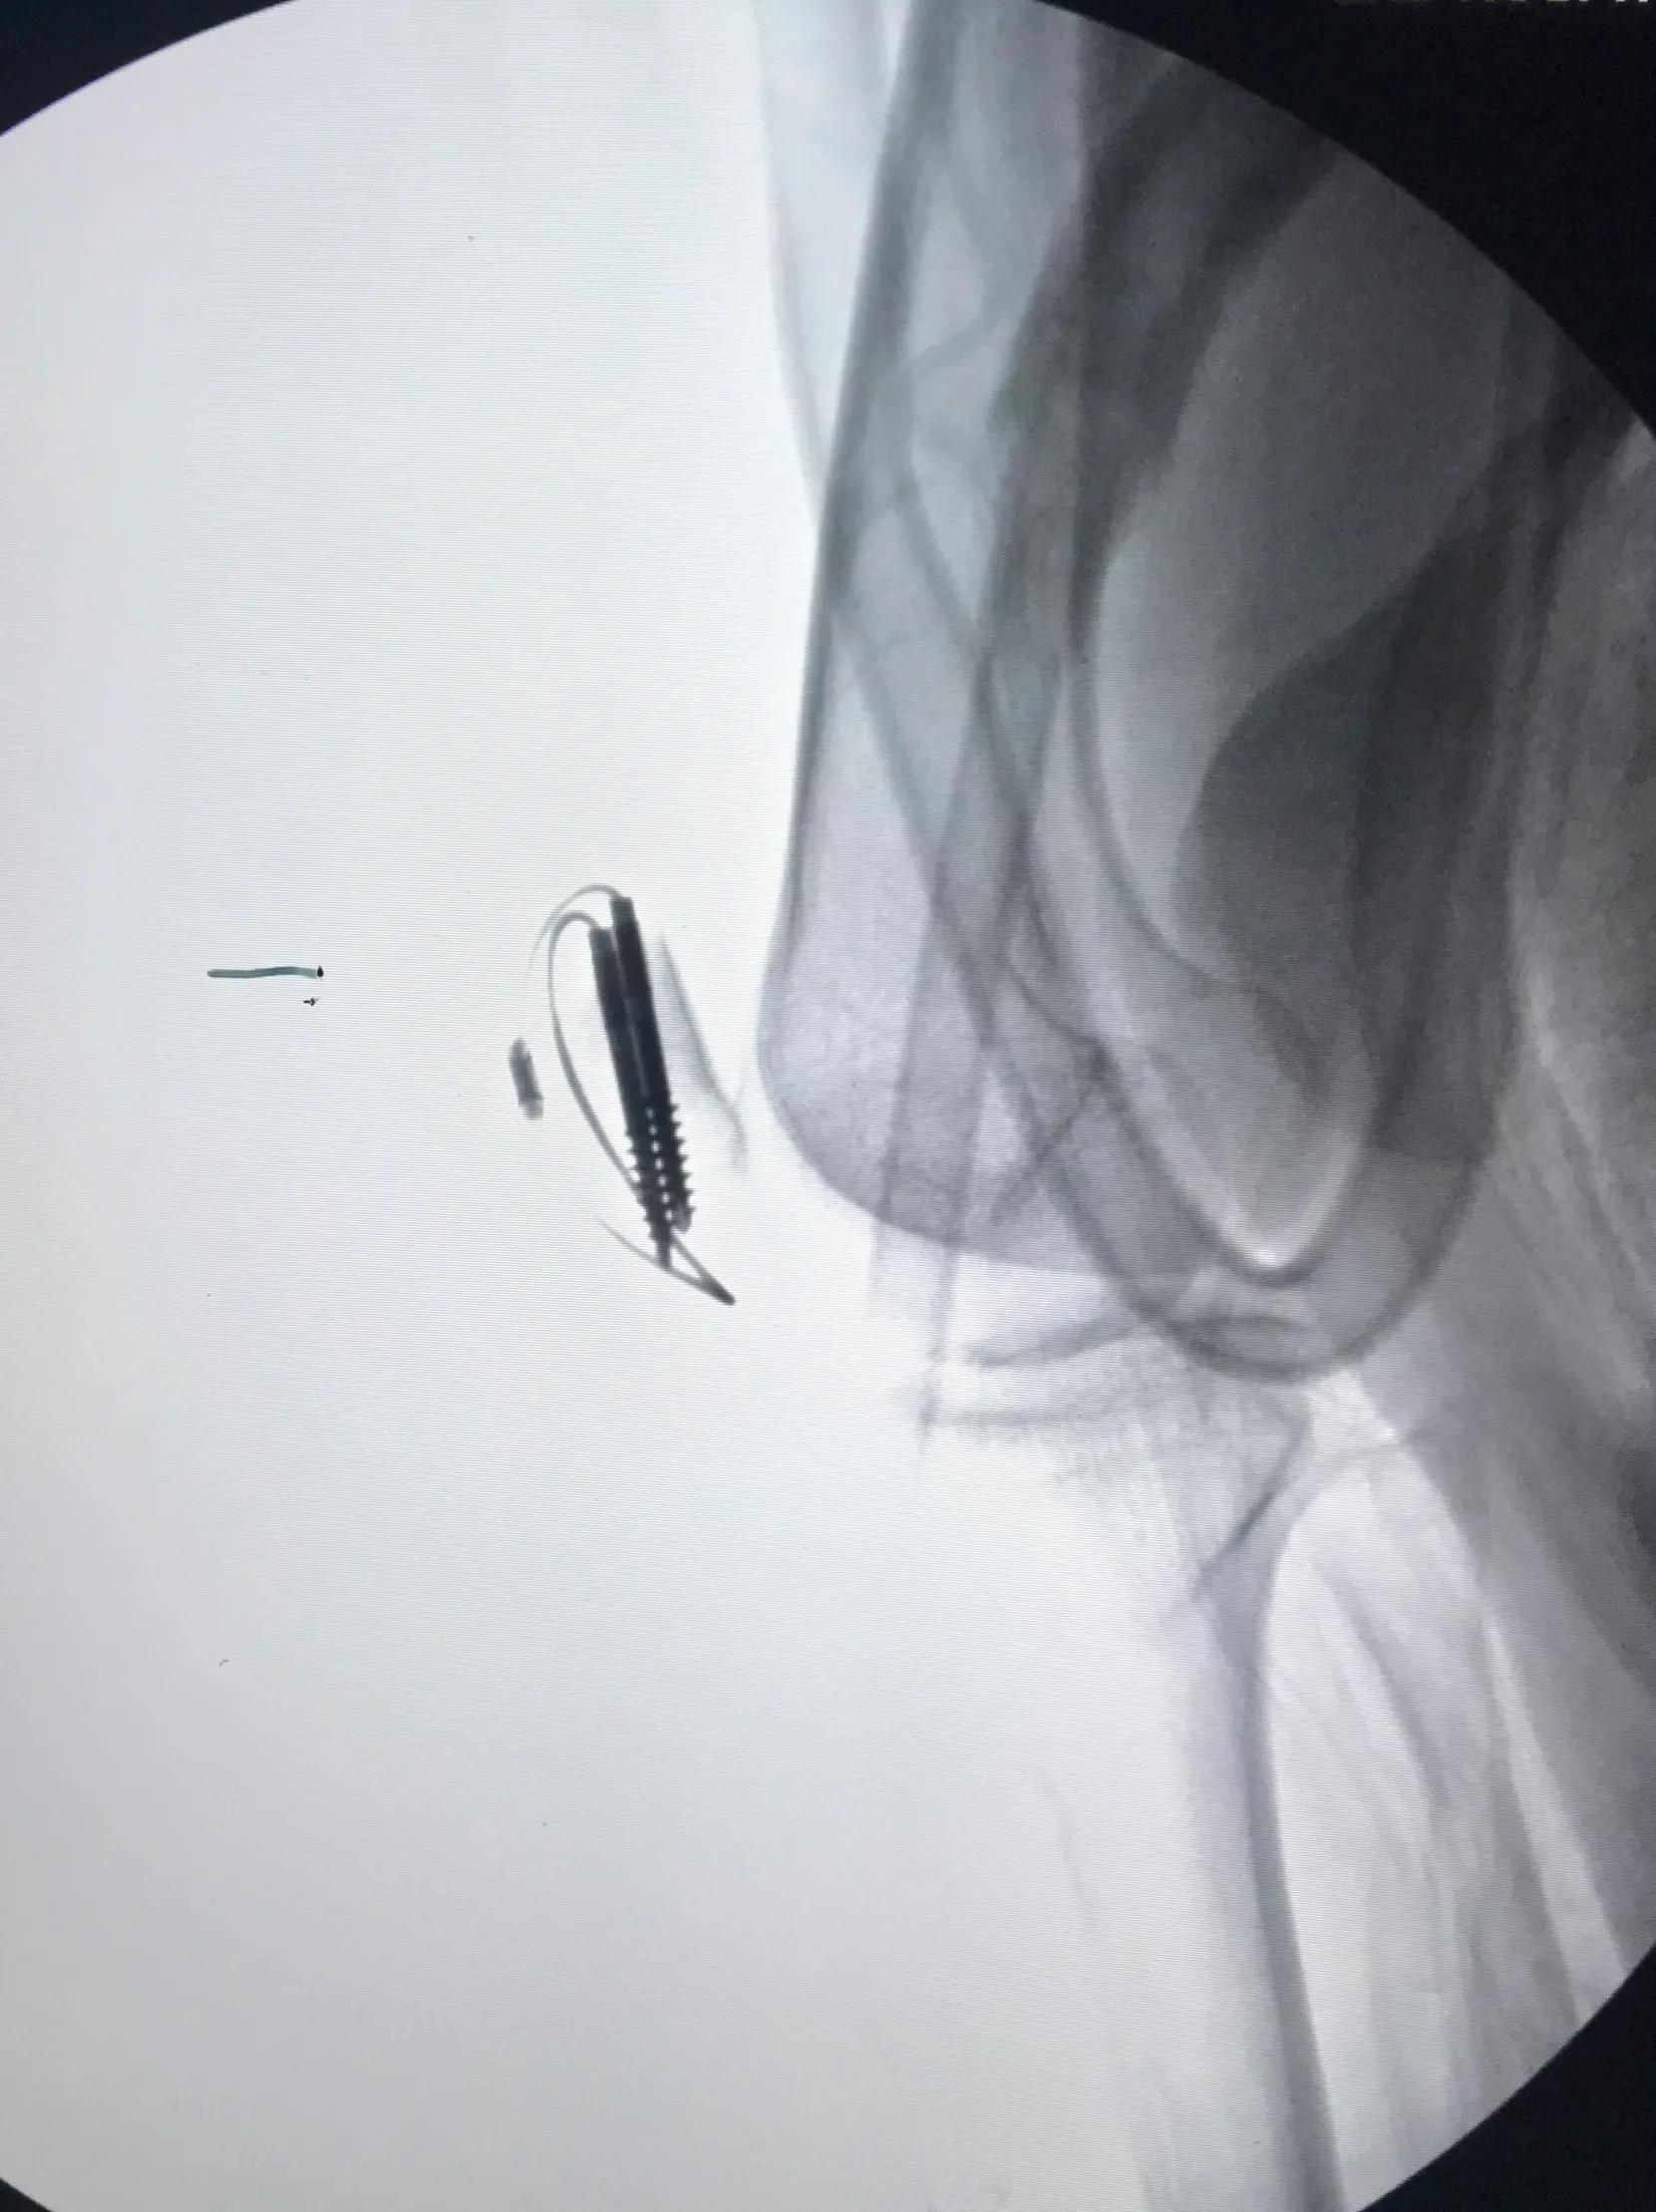

患者腰麻成功后,取平卧位,常规消毒铺巾,取膝关节纵行切口,约 10.0cm,逐层分离皮下组织及筋膜,完整暴露髌骨。复位后,应用大巾钳临时固定骨折块。C 型臂 X 光机透视下观察髌骨关节面是否平整,然后屈膝 90°,紧贴髌骨关节面由髌骨下极向上,垂直于髌骨骨折线平行打入 2 枚导针后,再次应用 C 型臂 X 光机检查导针位置。随后沿导针拧入 2 枚长度约等于髌骨纵行长度的空心拉力螺钉,拔出导针后,从空心钉内穿入钛缆,于髌前“8”字交叉,收紧钛缆并锁紧,剪除多余钛缆后,活动膝关节,检查固定的牢固性。术中需修补撕裂的髌韧带扩张部及筋膜。生理盐水冲洗手术切口后,放置引流管,逐层缝合手术切口,加压包扎。

手术中注意事项:(1)空心钉置钉位置应位于髌骨中份,最好两枚螺钉平行置钉,若螺钉偏髌骨前部,易导致关节面部分骨质失去加压作用;(2)钻入导针时最好一次成功,多次钻孔可能因钉道扩大,降低螺钉把持力;(3)空心钉应平行关节面,螺纹应完全跨越骨折线,否则不能起到初始加压作用;(4)空心钉头尾两端最好埋入髌骨内,使钛缆对髌骨起到张力带作用,避免应力传到螺钉上和钉头端切割钛缆,导致内固定失败;(5)在锁紧锁扣前,充分活动膝关节,检查骨折的稳定性和钛缆的松紧程度。